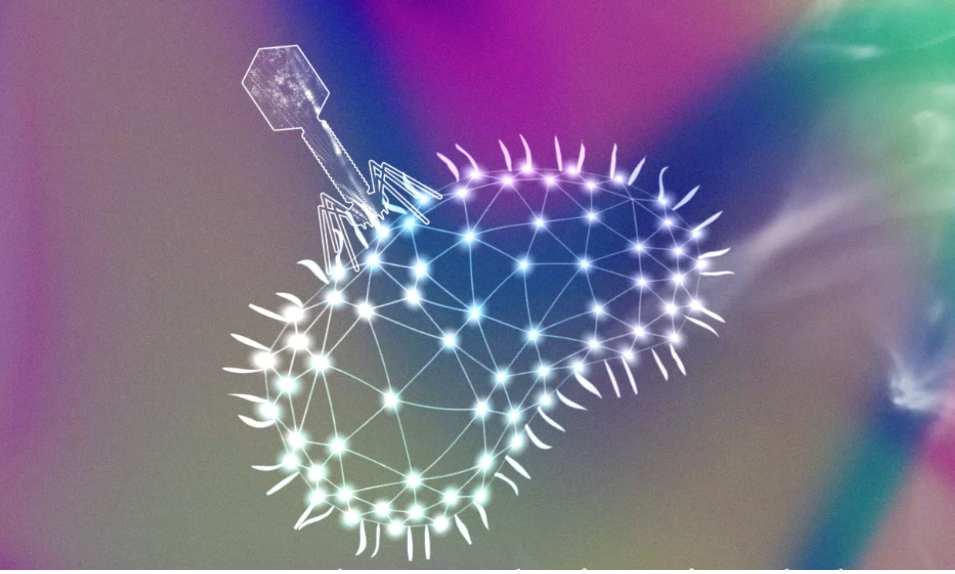

Les bactériophages, vers une alternative ciblée aux antibiotiques

Avec l’essor des antibiotiques dans les années 1930, la phagothérapie a été abandonnée. Aujourd’hui, la montée de l’antibiorésistance rend le traitement des infections bactériennes de plus en plus difficile et la phagothérapie suscite à nouveau l’intérêt des médecins...